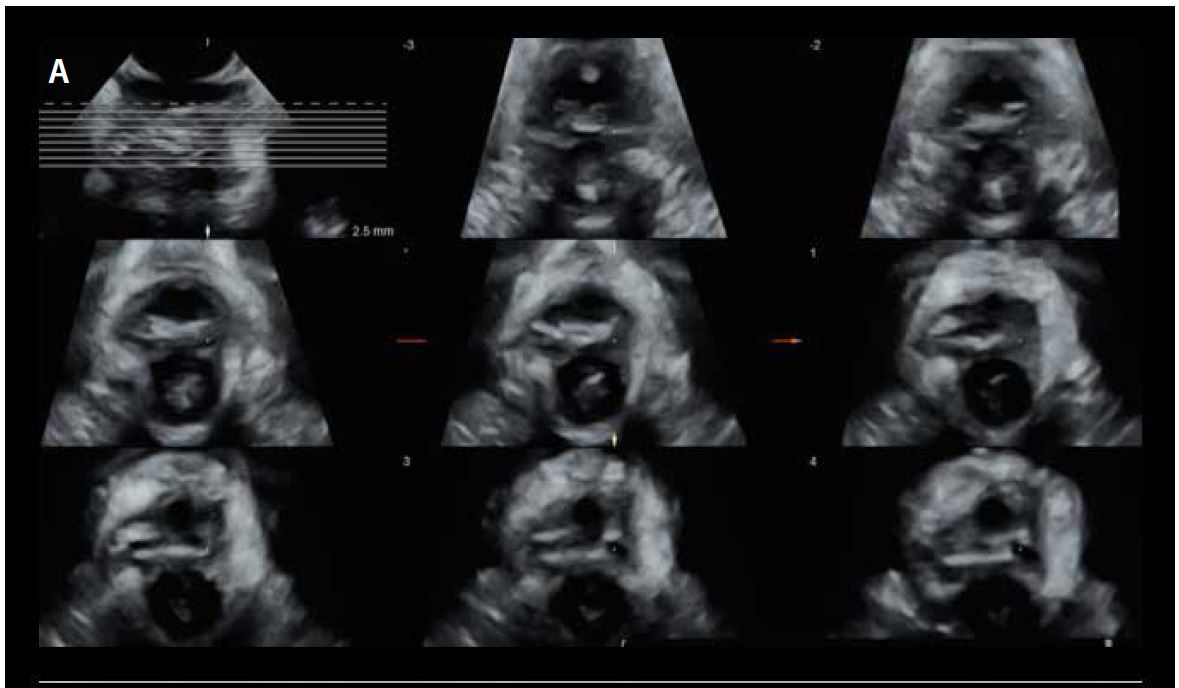

Мультиплощинна реконструкція з площини мінімальних гіатальних розмірів (мал. 10) є стандартизованим і еталонним способом оцінки авульсії LAM. Осьові площини отримують з інтервалом 2,5 мм (5 мм каудально і 12,5 мм краніально), оцінюючи загалом 8 площин (мал. 11). Точне розташування 8 площин встановлюється по трьох центральних площинах (жовта пунктирна лінія на мал. 11):

• 1st прощина (зліва): дуги лобкового симфізу розділені.

• 2nd площина (центральна): дуги лобкового симфізу зімкнуті.

• 3rd площина (справа): лобок не повинен відображатися, заміняючись акустичною тінню.

Малюнок 11. Багатоплощинна реконструкція м'язу-підіймача відхідника (LAM) з трьома центральними площинами, виділеними жовтим.